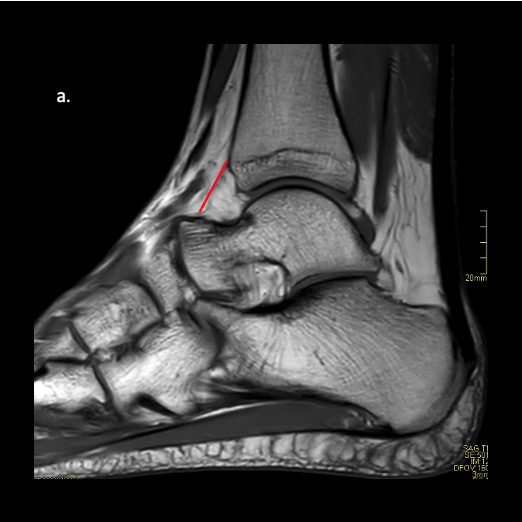

Now to the MRIs: I recommend one reviews the T1 and T2 sagittal images first. The T1 will be very helpful in assessing the joint morphology, and T2 will aid in determining the location and volume of the anterior and posterior joint capsule. Once we can start identifying pathology, we can then pinpoint the true location by triangulating with the coronals for medial/lateral positioning.

My focus is simple: I want to highlight commonly missed MRI pathology. It is probably not critical to identify what you see as much as recognizing that this structure or signal is abnormal (Figure 3). That is critical for educating patients. So when you see a large object or structure that shouldn’t be there, the patient will be able to comprehend why their ankle actually hurts, clicks, pops, or locks up. This educates not just our patients but ourselves on the benefits of surgery.